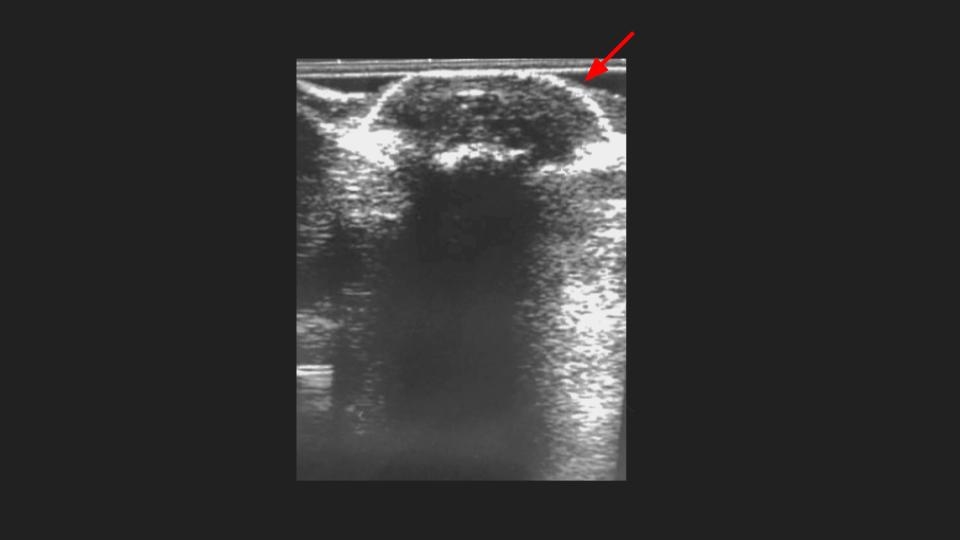

Aspirated and proven Gout of the first toe interphalangeal joint.

There is an intermediate T1 / Bright PDFS, STIR signal mass dorsal to the hallux IP with subtle erosion (arrow in short axis MRI) and no BME. No joint space narrowing, mild IPJ synovitis (not shown). XRs and US send as screenshots from referrer. She aspirated whitish greenish material from the dorsal IPJ mass/collection.